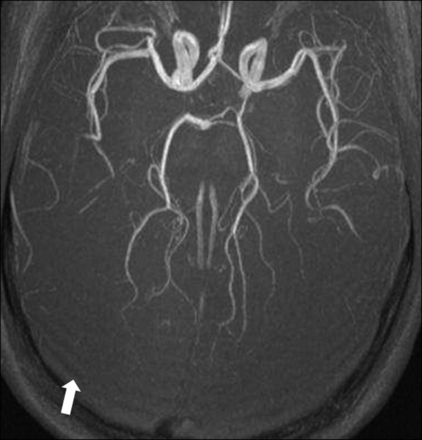

Ringing artifacts (arrow) at the back of the brain of a 4-week-old full-term neonate on an axial maximum intensity projection of an optimized neonatal MR angiography protocol79 acquired at 3T. Ringing artifacts occur due to data undersampling, and should not be confused with motion-artifacts ghosts.